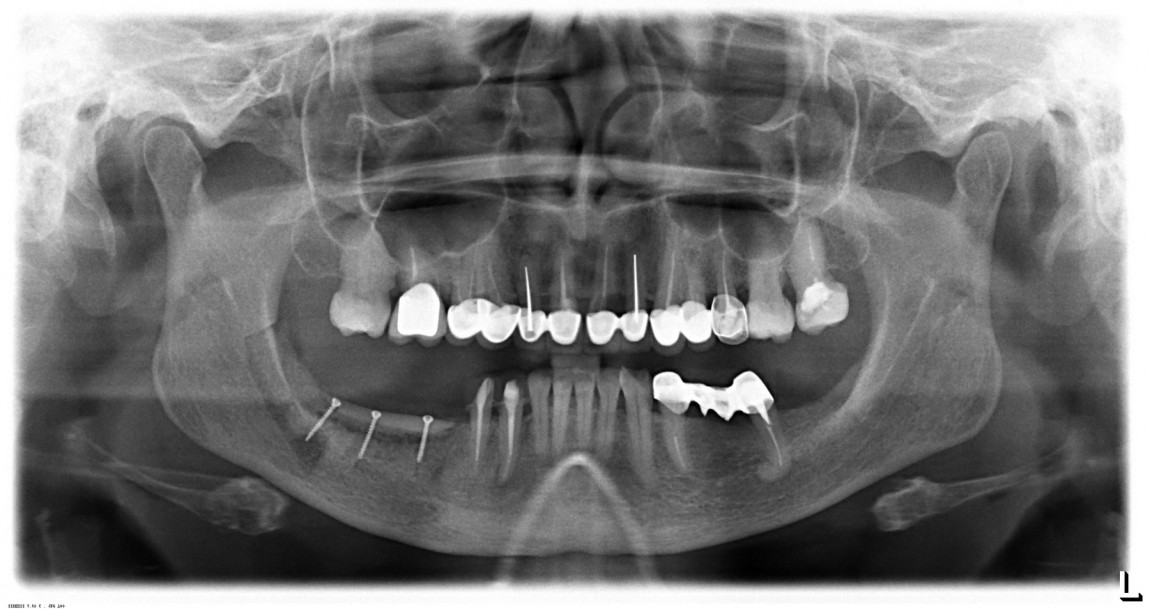

Метод аутотрансплантации костных блоков - насколько он результативен в долгосрочной перспективе? Я покажу тебе результаты остеопластики через 12 лет после операции, а выводы ты сделаешь самостоятельно.

Когда можно оценить результат остеопластической операции? И что вообще можно считать её результатом? Мы представляем вашему вниманию историю нашей пациентки - и на её примере ответим на вышеуказанные вопросы. Кстати, а как это согласуется с тем, что мы писали о наращивании костной ткани раньше?

Cовременными методами остеопластических операций мы можем воссоздать ЛЮБОЙ объем костной ткани в ЛЮБОМ месте зубного ряда. Нюанс лишь в методе операции и сроке, необходимом для нормального восстановления кости.

Предлагаю рассмотреть остеопластическую методику - восстановление объемов костной ткани с использованием аутокостной стружки, биоматериалов и барьерных мембран.